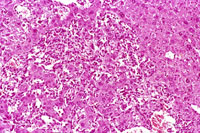

This hemangiosarcoma is has caused degenerative changes in some of the entrapped hepatocytes. The degenerating hepatocytes are enlarged and vacuolated with evidence of nuclear degeneration.